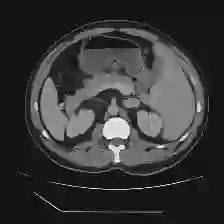

Medical image segmentation is one of the most fundamental tasks concerning medical information analysis. Various solutions have been proposed so far, including many deep learning-based techniques, such as U-Net, FC-DenseNet, etc. However, high-precision medical image segmentation remains a highly challenging task due to the existence of inherent magnification and distortion in medical images as well as the presence of lesions with similar density to normal tissues. In this paper, we propose TFCNs (Transformers for Fully Convolutional denseNets) to tackle the problem by introducing ResLinear-Transformer (RL-Transformer) and Convolutional Linear Attention Block (CLAB) to FC-DenseNet. TFCNs is not only able to utilize more latent information from the CT images for feature extraction, but also can capture and disseminate semantic features and filter non-semantic features more effectively through the CLAB module. Our experimental results show that TFCNs can achieve state-of-the-art performance with dice scores of 83.72\% on the Synapse dataset. In addition, we evaluate the robustness of TFCNs for lesion area effects on the COVID-19 public datasets. The Python code will be made publicly available on https://github.com/HUANGLIZI/TFCNs.